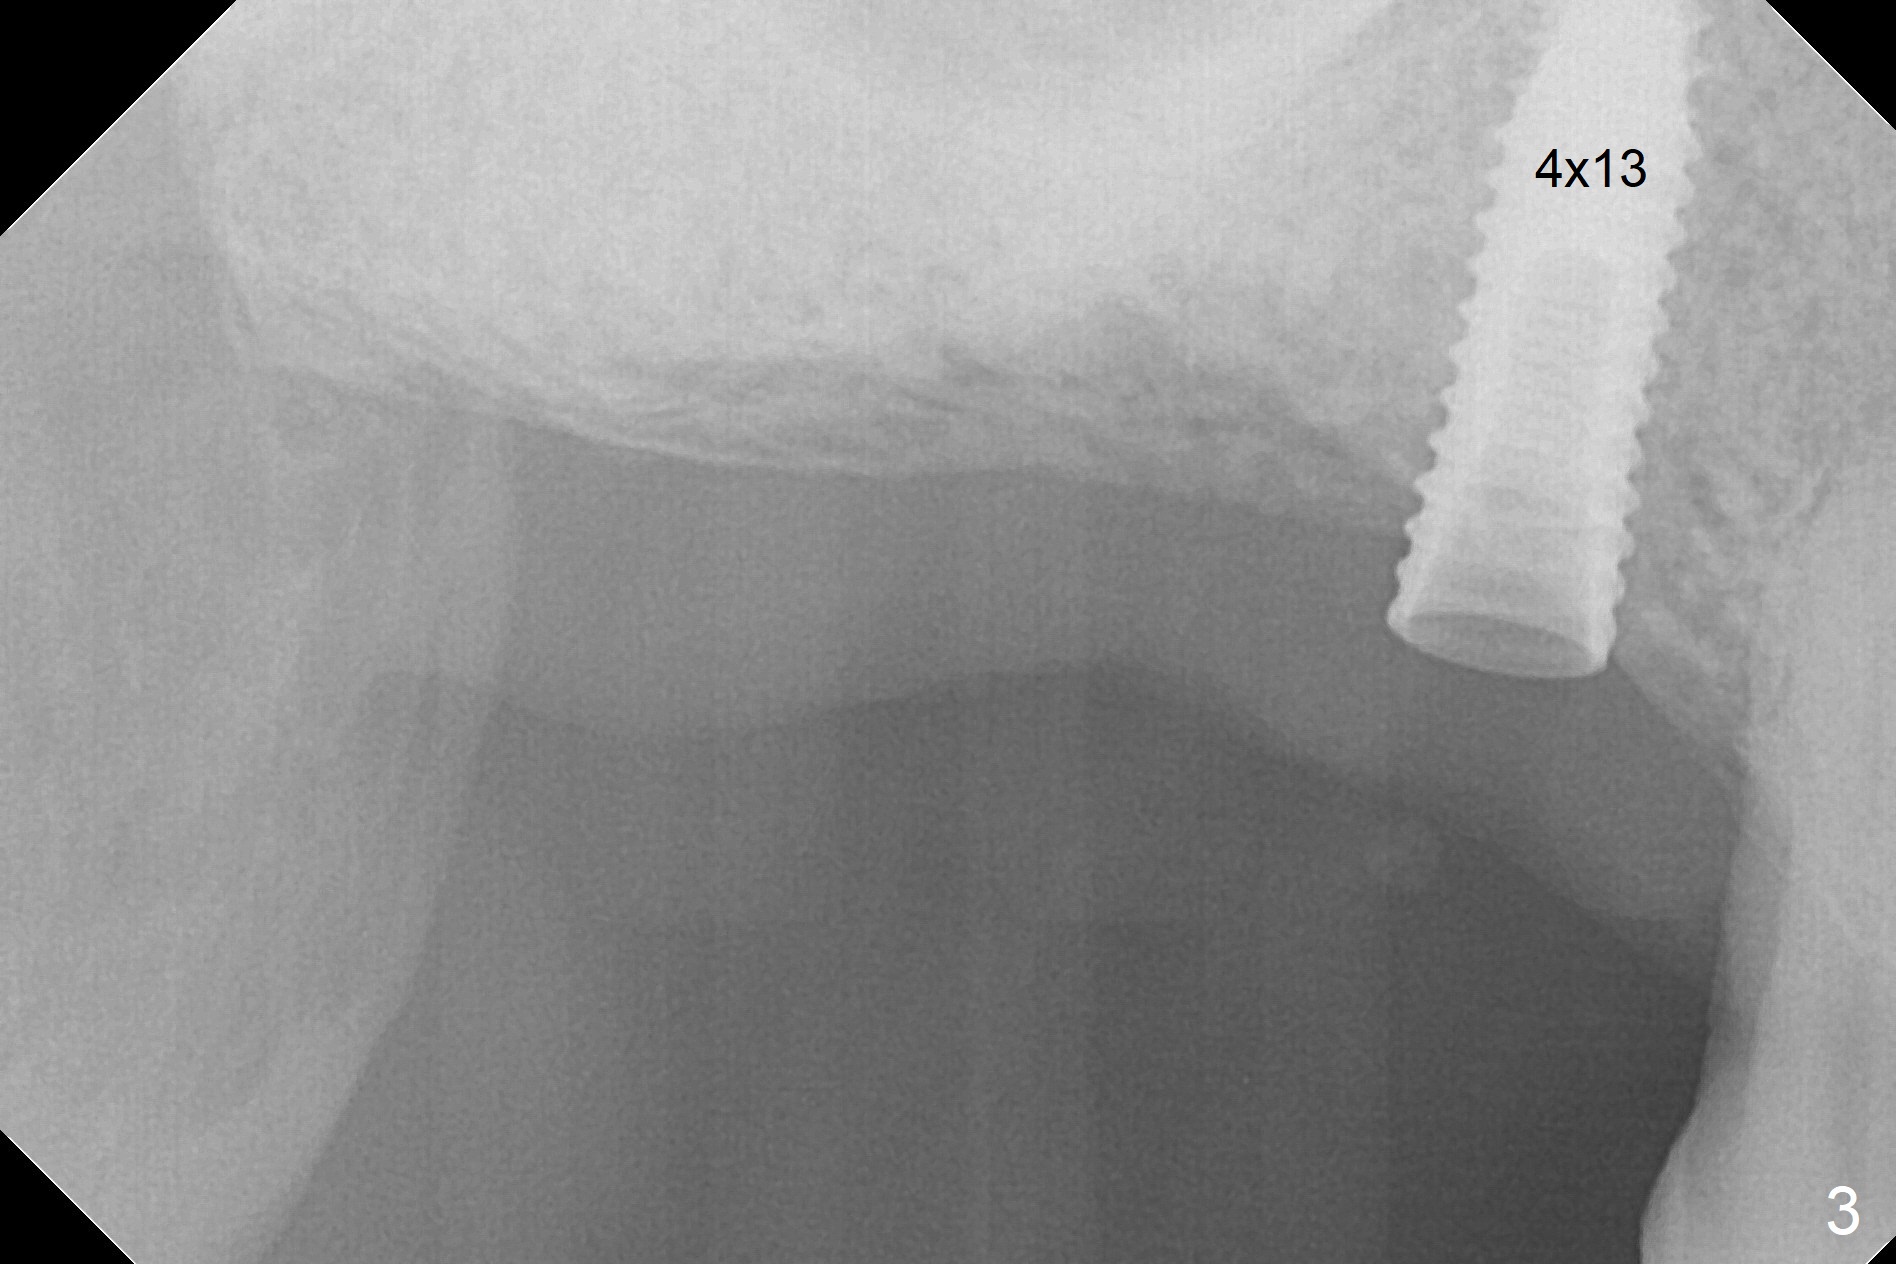

Bone Expansion Alternates with Drill

Since the ridge crest at #3 is narrow, Tatum bone scalpels are used to get access and initiate bone expansion, followed by bone blades and RT 2.  It seems that the osteotomy starts mesially; bone height being increased (Fig.1).  When the apical end of the osteotomy tilts mesially, more bone height is obtained.  Drills are alternatively applied because of the hard bone (Fig.2).  A 4x13 mm UF implant is placed initially with the distal threads unburied (Fig.3, >50 Ncm).  With further seating of the implant, a 5.5x5(4) mm abutment is used (Fig.4), which closes the access.  No suture is warranted.  An immediate provisional is fabricated for the patient's comfort and psychological effect.  In fact, the abutment cuff changes to 5 mm prior to temporarization.  There appears no bone loss <4 months postop (Fig.5).  Pulpitis develops at #4 due to DO caries 1 year 5 months post cementation (Fig.6 *).  The crown at #3 is removed for easy and conservative distal carious removal and Cavit temporary restoration to prevent sodium hypochlorite leakage.  Then occlusal access is made for pulpotomy.  When RCT finishes, no crown will be made, but occlusal reduction is required.    The patient returns for RCT 1 month later (Fig.7,8). Cavit remains in place (Fig.7 C).  Although 2 threads are exposed distal (Fig.8 arrow), there is no sign or symptom of periimplantitis, which may be related to the thick gingiva (arrowhead).  Return to Upper Molar Immediate Implant, IBS, #14 (Tissue Punch) Xin Wei, DDS, PhD, MS 1st edition 08/25/2017, last revision 09/08/2019